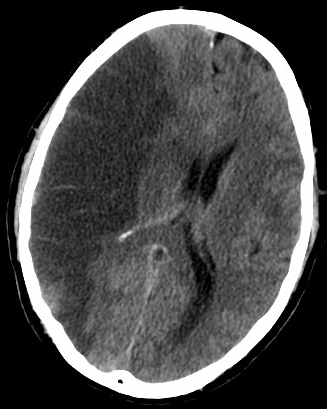

Tomografia komputerowa

Tomografia komputerowa to technika obrazowania medycznego stosowana do uzyskiwania szczegółowych obrazów wewnętrznych ciała. >>>

Tomografia komputerowa to badanie diagnozujące także w innych stanach chorobowych, jak np.: marskość wątroby, kamica żółciowa, zapalenie pęcherzyka żółciowego, beryloza, zapalenie wyrostka robaczkowego, przepuklina pępowinowa, wrzodziejące zapalenie jelita grubego, alkoholowe zapalenie wątroby, tętniak, choroba moyamoya, Żylaki przełyku, zapalenie płuc, zawał mięśnia sercowego, zatorowość płucna, krwotok podpajęczynówkowy, krwotok śródmózgowy, choroba Wilsona, sarkoidoza, rak nerki, rak pęcherza moczowego, siatkówczak, mięśniakomięsak prążkowanokomórkowy, glejak wielopostaciowy, rak szyjki macicy, rak jajnika, rak żołądka, rak jelita grubego, rak odbytu, rak dróg żółciowych, rak trzustki, rak płuc, rak serca, rak kości, mięsak Kaposiego, gnatostomoza, rak przełyku, histoplazmoza, ornitoza, japońskie zapalenie mózgu, nokardioza, zgorzel gazowa, legionelloza, gruźlica, blastomykoza, rak jądra, sARS, bąblowica, choroba niedokrwienna serca, idiopatyczne włóknienie płuc.